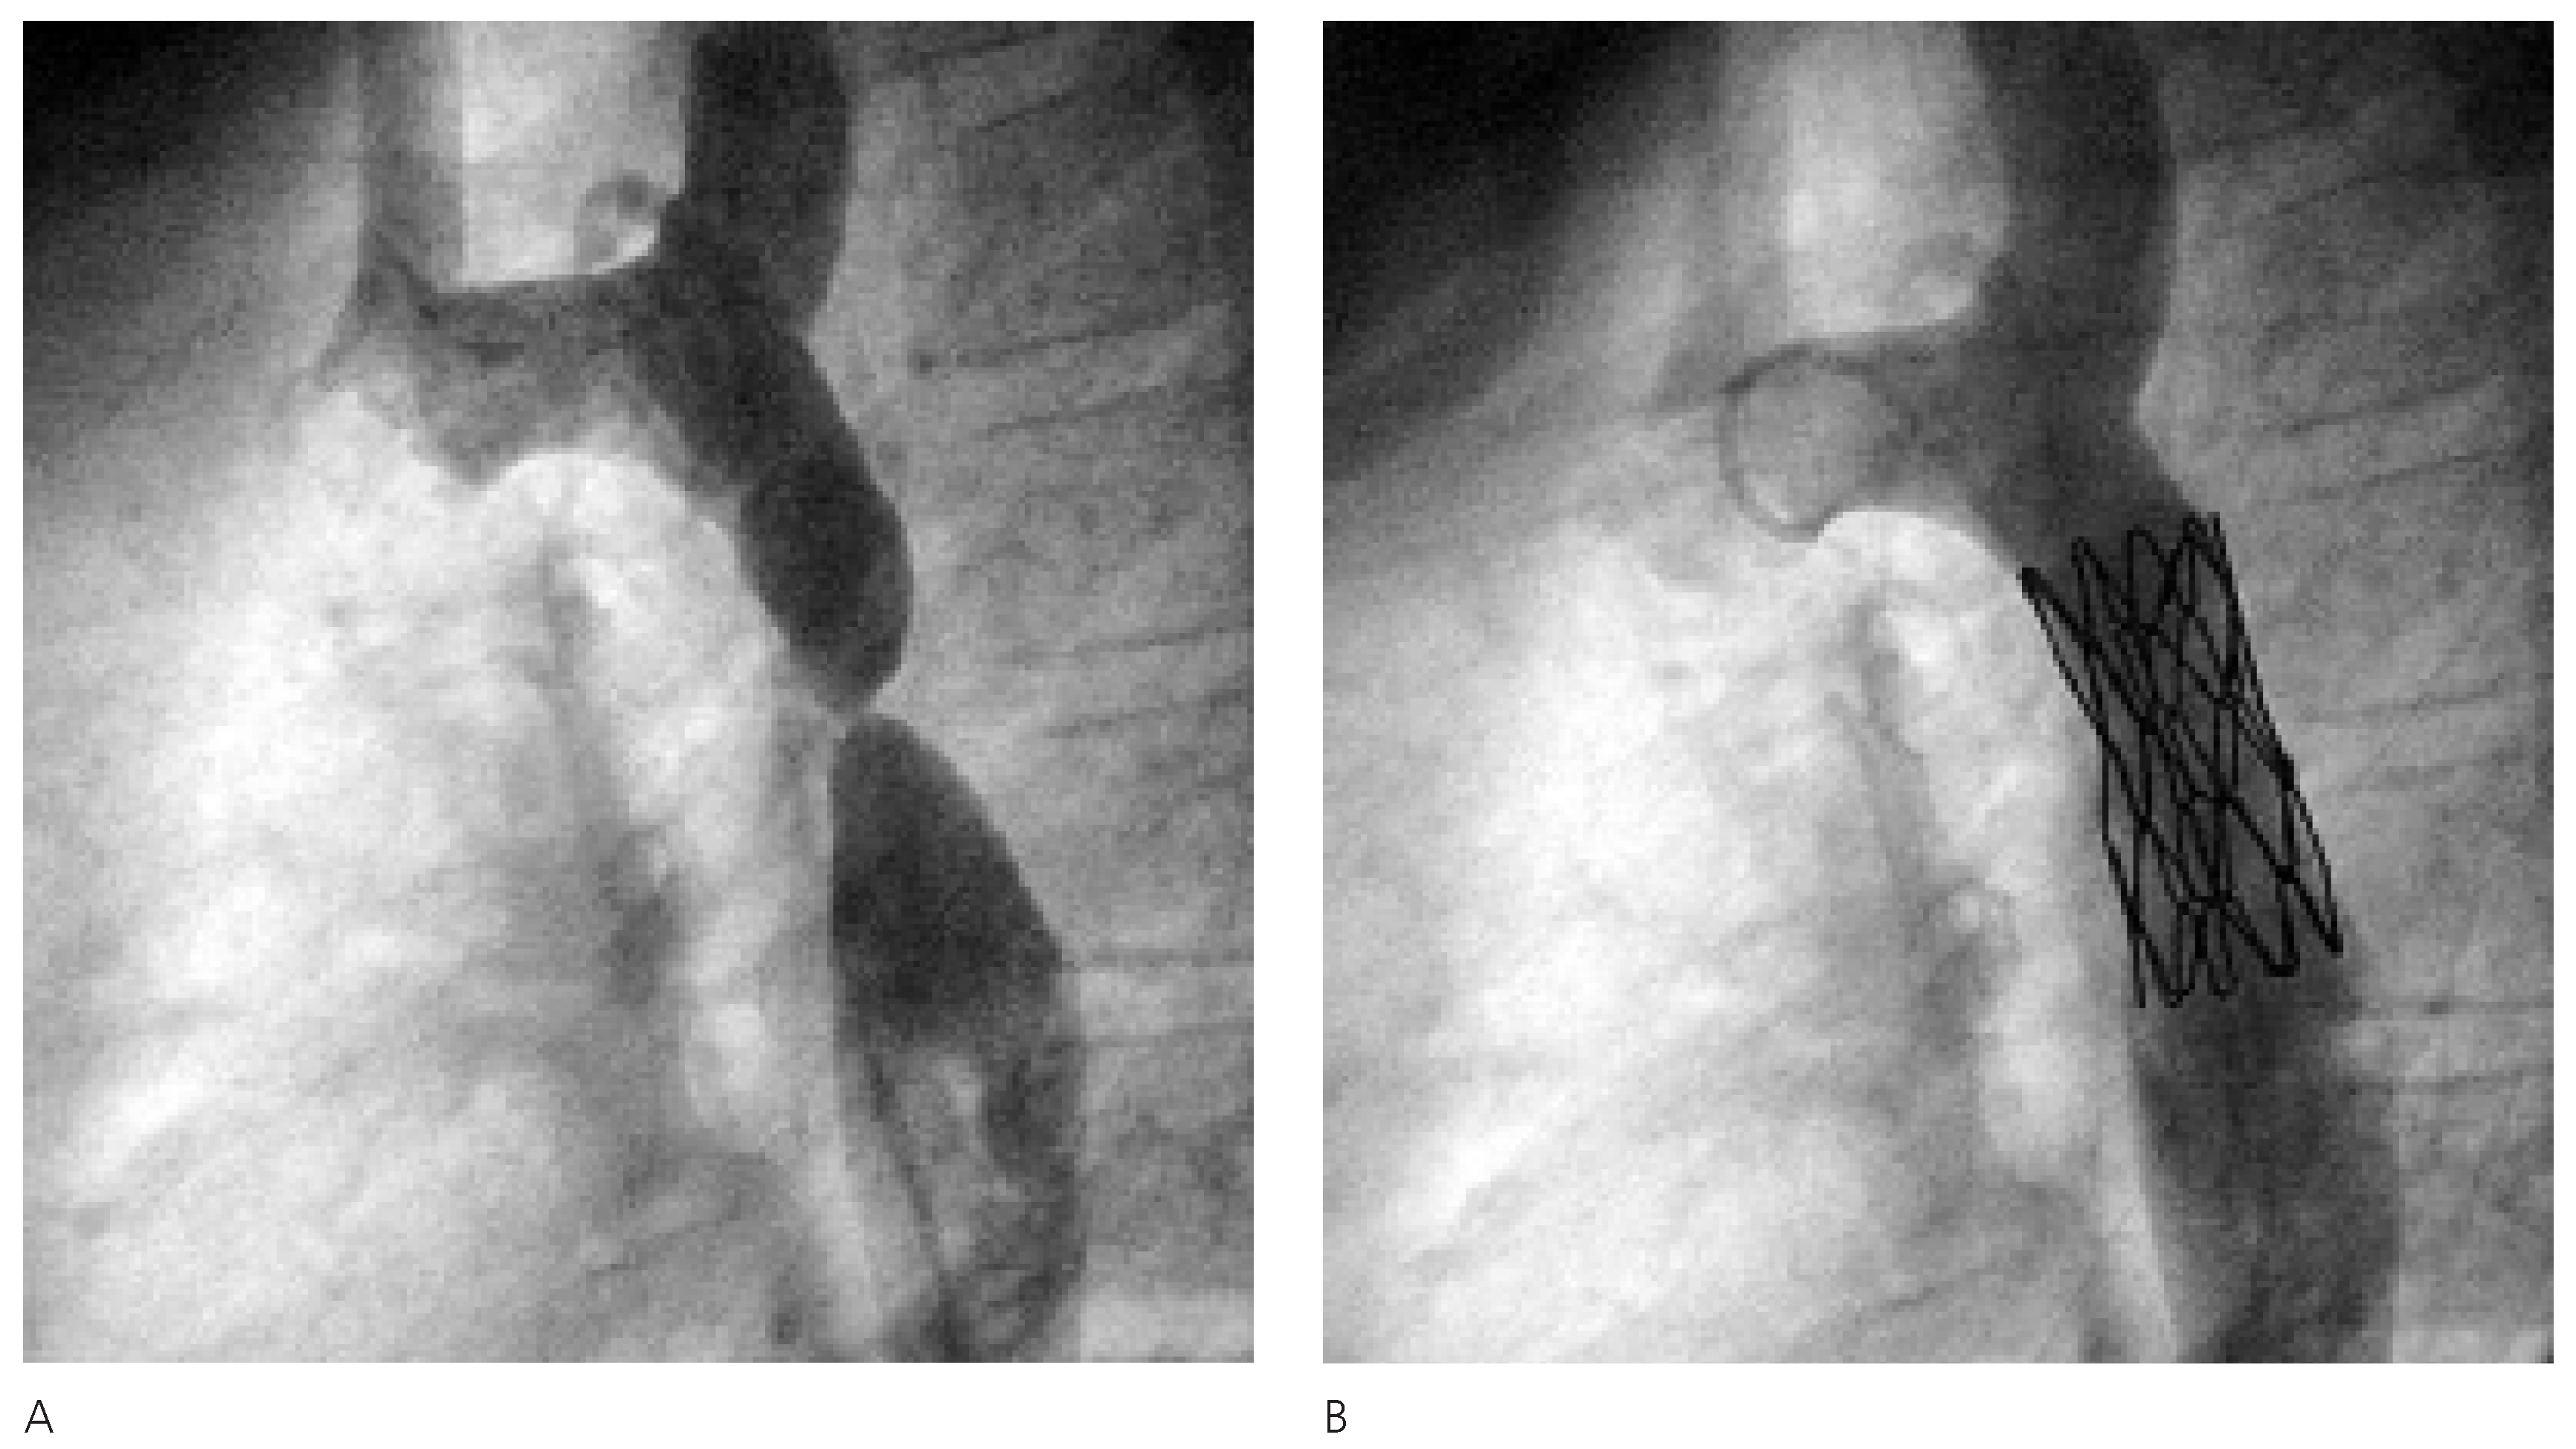

Die katheterinterventionelle Therapie gestaltete sich als komplikationslose Stent-Implantation mit Erweiterung des Aortenlumens im Bereich der AIS von knapp 1,4 mm auf 12 mm und entsprechender Reduktion des Druckgradienten von initial 40 mm Hg auf 5 mm Hg (Figure 3).

Figure 3.

Angiographische Darstellung der hochgradige Stenose (A) und postinterventionelles Resultat mit korrekter Position des Stentes und vollständiger Behebung der Einengung (B).